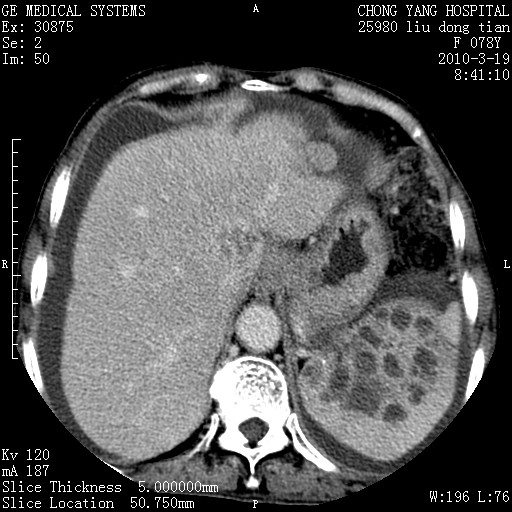

标题: CT25199:F 78Y 腹胀半年 消瘦乏力 [打印本页]

胆囊壁增厚并明显强化,胆囊癌伴多发转移瘤可能性大,淋巴瘤不除外,右肾囊肿,胸腹水.

考虑nhl,肝、脾、腹膜腔及腹膜后多发淋巴结受侵,腹水,右肾囊肿,慢性胆囊炎,右侧少量胸腔积液。

胰头有肿块形成,胰头ca伴肝脾、腹膜腹膜后转移

胆囊有软组织影有强化,支持胆囊癌,肝脾、腹膜后淋巴结转移。

nhl的淋巴结多围绕主动脉,而且主动脉会移位,所以不考虑nhl。

分开来讲:肝左叶、尾叶病灶有不均强化像肝癌;

肝门、胰腺头、腹膜后多个团块: 淋巴瘤,转移;

最后报的胰头癌多发转移,脾脏单独考虑囊肿或淋巴管瘤。